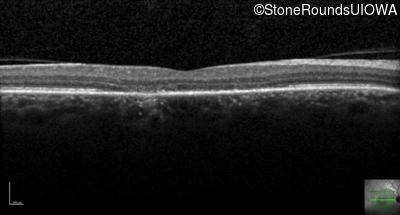

This 44 year old man became photophobic about 6 years ago. He has been taking Imuran since his kidney transplant 23 years ago.

| Senior-Loken Syndrome | NPHP1 | Gly343Arg G(GG)>A(GG) | Deletion of Entire Gene | AR |